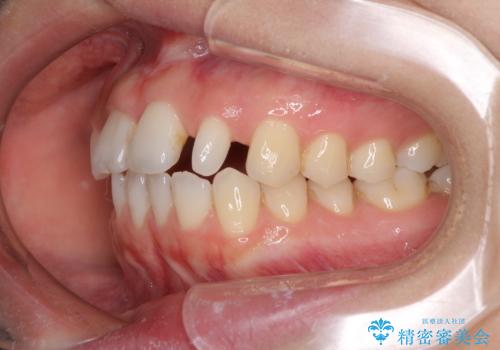

欠損歯と矮小歯 矯正治療と前歯のセラミック治療

- 前歯の隙間を気にして来院された患者様です。

診察の結果、前歯が1本欠損しており、さらに矮小歯(通常よりも小さい歯)が1本存在していました。

欠損による前歯のスペースが大きかったため、事前にワイヤー矯正で前歯の位置を大きく動かし、その後は上下をインビザラインで整えることとしました。

矯正治療後には欠損部はオールセラミックブリッジに、矮小歯はオールセラミッククラウンにて補綴することとしました。

前歯のスペースは、堅い線維の通った歯肉があり、幅も大きかったことから、歯肉切除を行った上でワイヤー矯正により移動を行いました。また、上唇小帯も歯間部付近まで付着していたため、合わせて切除しました。

ワイヤー矯正により、インビザラインよりも早く、歯軸の向きもコントロールしながら移動させることができました。